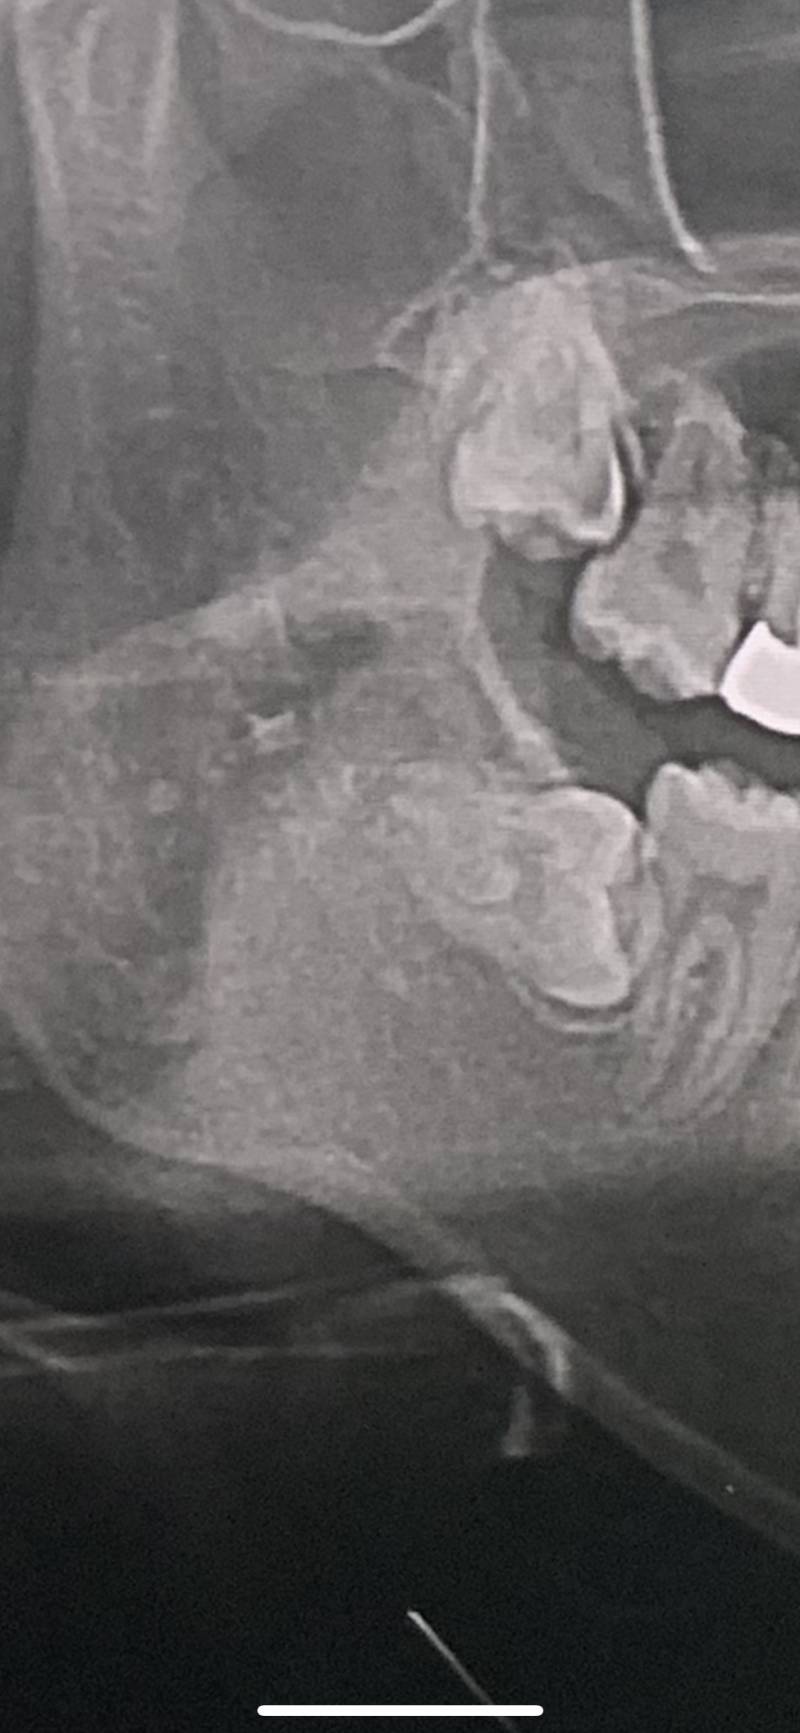

내 사랑니 봐줘 완전 특이하지 않아 ? ㅠㅠ40

이렇게 누워서 나는거는 처음 봐 ...

ㅇㄴ.......

ㅠㅠㅠㅠ징그러워? 미안행

아니 징그러운게 아니라 쓰니가 고생 많이할것같어서...

뺄 때 아프겠다ㅠㅠㅠ

첫번째 완전 내 사랑닌데?.. 진짜 지옥이다..조심해,,,

나도 사랑니 저렇게 났었는데 뺐당..

ㅠㅠㅠㅠㅠ사랑니 빼는거 어때? 참을만해...?

마취주사 맞아서 빼는거 자체는 안 아픈데 마취할때 놓는 주사기가 진짜 크고 그래서 아파.. 그리고 마취 풀리고 나서가 진짜 헬이었어ㅠ

나도 아래 사랑니 다 저렇게 누워서 앞에 치열 망가뜨리길래 뺐다ㅠ

사랑니 빼는거 많이 아프니 ...?

마취만 잘 들면 하나도 안 아파!